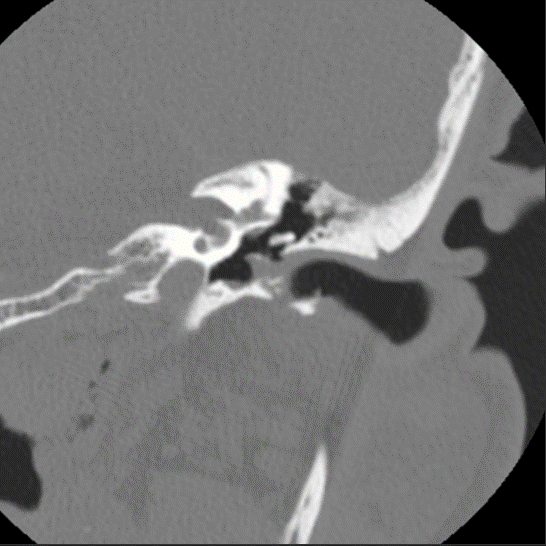

Classic EAC cholesteatoma. Axial bone algorithm shows soft tissue density within the medial left EAC with boney erosion and characteristic bone flakes.